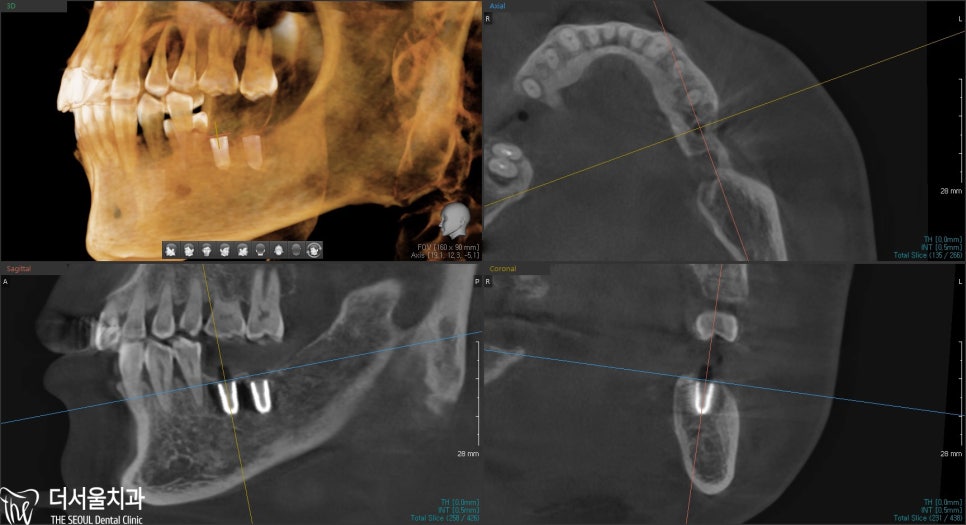

임플란트 픽스처 식립에 앞서

수정구 태평동 치과 의료진은

컴퓨터 분석 프로그램 및 3D CT를 통하여

픽스처를 심을 정확한 위치 및 각을 체크하여

좋은 결과가 이뤄질 수 있도록

꼼꼼히 확인했습니다.

게다가 아랫니는 하치조 신경이라는 것을

건드리지 않도록 조심해야 되기에

그와의 거리 또한 체크했습니다.

다행스럽게도 크게 문제될 것이 없었기에

어떤 각으로 얼마만큼 깊게 심으면 좋을지

확인한 뒤에 수술을 진행했습니다.